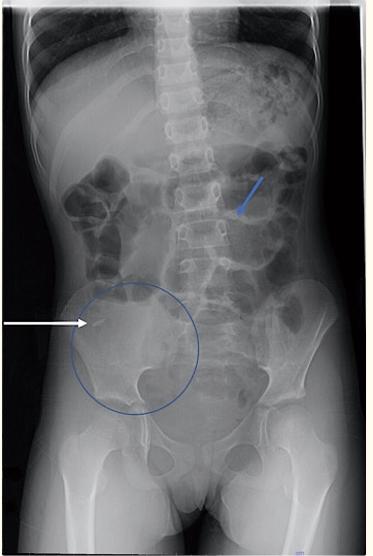

初步检查包括全血细胞计数、腹部X线和腹部超声(US)及平片(图1)。初始白细胞计数为19.6×109/L 腹部超声显示回结肠肠套叠,肠套叠部位有致密碎屑(与沙子一致)(图2)。腹部X光显示右下象限气体缺乏,与回结肠肠套叠的推测诊断相符。患儿被转诊以进一步治疗。

图1、初始X光照片显示右下象限的软组织密度(蓝色圆圈)。其内部呈线性高密度,代表沙子的凝结体(白色箭头)。小肠和大肠的充气环扩张是发展中的梗阻的隐患(蓝色箭头)